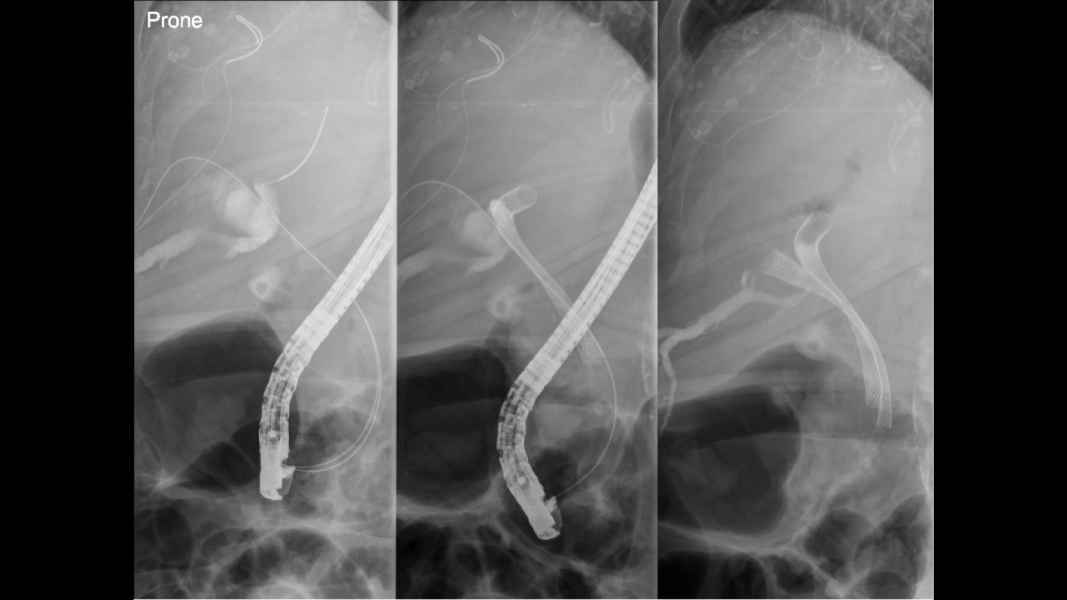

Estenose de Anastomose Hepatico-jejunal com litíase intra-hepática – Tratamento por CPRE com Enteroscópio

Fotografia